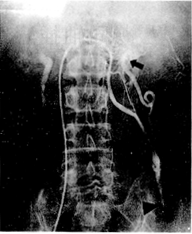

摘要 为了减少精索静脉曲张经皮硬化栓塞术中的复发因素,提高硬化剂治疗的效果,从1991年3月至1995年6月使用同轴插管方法,进行精索静脉远端主干和近端侧支血管的硬化栓塞,共治疗左侧精索静脉曲张23例,精索静脉近端插管全部成功,远端插管的成功率为78.0%,栓塞后的显效率为95.6%,无并发症。平均随访14个月未见复发。认为该方法可准确、安全、高效地进行精索静脉曲张的硬化治疗。

Abstract From March 1991 to June 1995,23 patients with left varicocele weretreated by percutaneous sclerotherapy with coaxial catheterization. Distal part andproximal collaterals of internal spermatic vein were occluded successfully in all patientswith no serious complication. Of 18 patients, the success rate of distal catheterizationhas been 78%. Varicoceles were greatly improved in 22 patients. Twenty-three patients werefollowed up for a period of 6~30 months and noreccurence has been found.